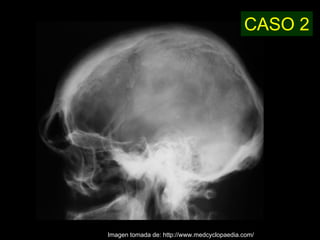

Este documento describe la acromegalia, una condición causada por un exceso de hormona de crecimiento producida por la hipófisis. Provoca un crecimiento anormal de las extremidades, la cara y los órganos internos. Sus síntomas incluyen prominencia de la mandíbula, las manos y los pies, así como engrosamiento de la piel y huesos. Generalmente se debe a un adenoma de la hipófisis y su diagnóstico se realiza mediante pruebas de sangre y resonancia magnética.